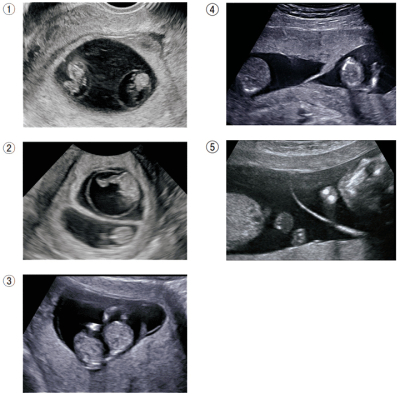

双胎妊娠の超音波検査の結果を別に示す。

2絨毛膜2羊膜性双胎と判断できるのはどれか。2つ選べ。

a. ①

b. ②

c. ③

d. ④

e. ⑤